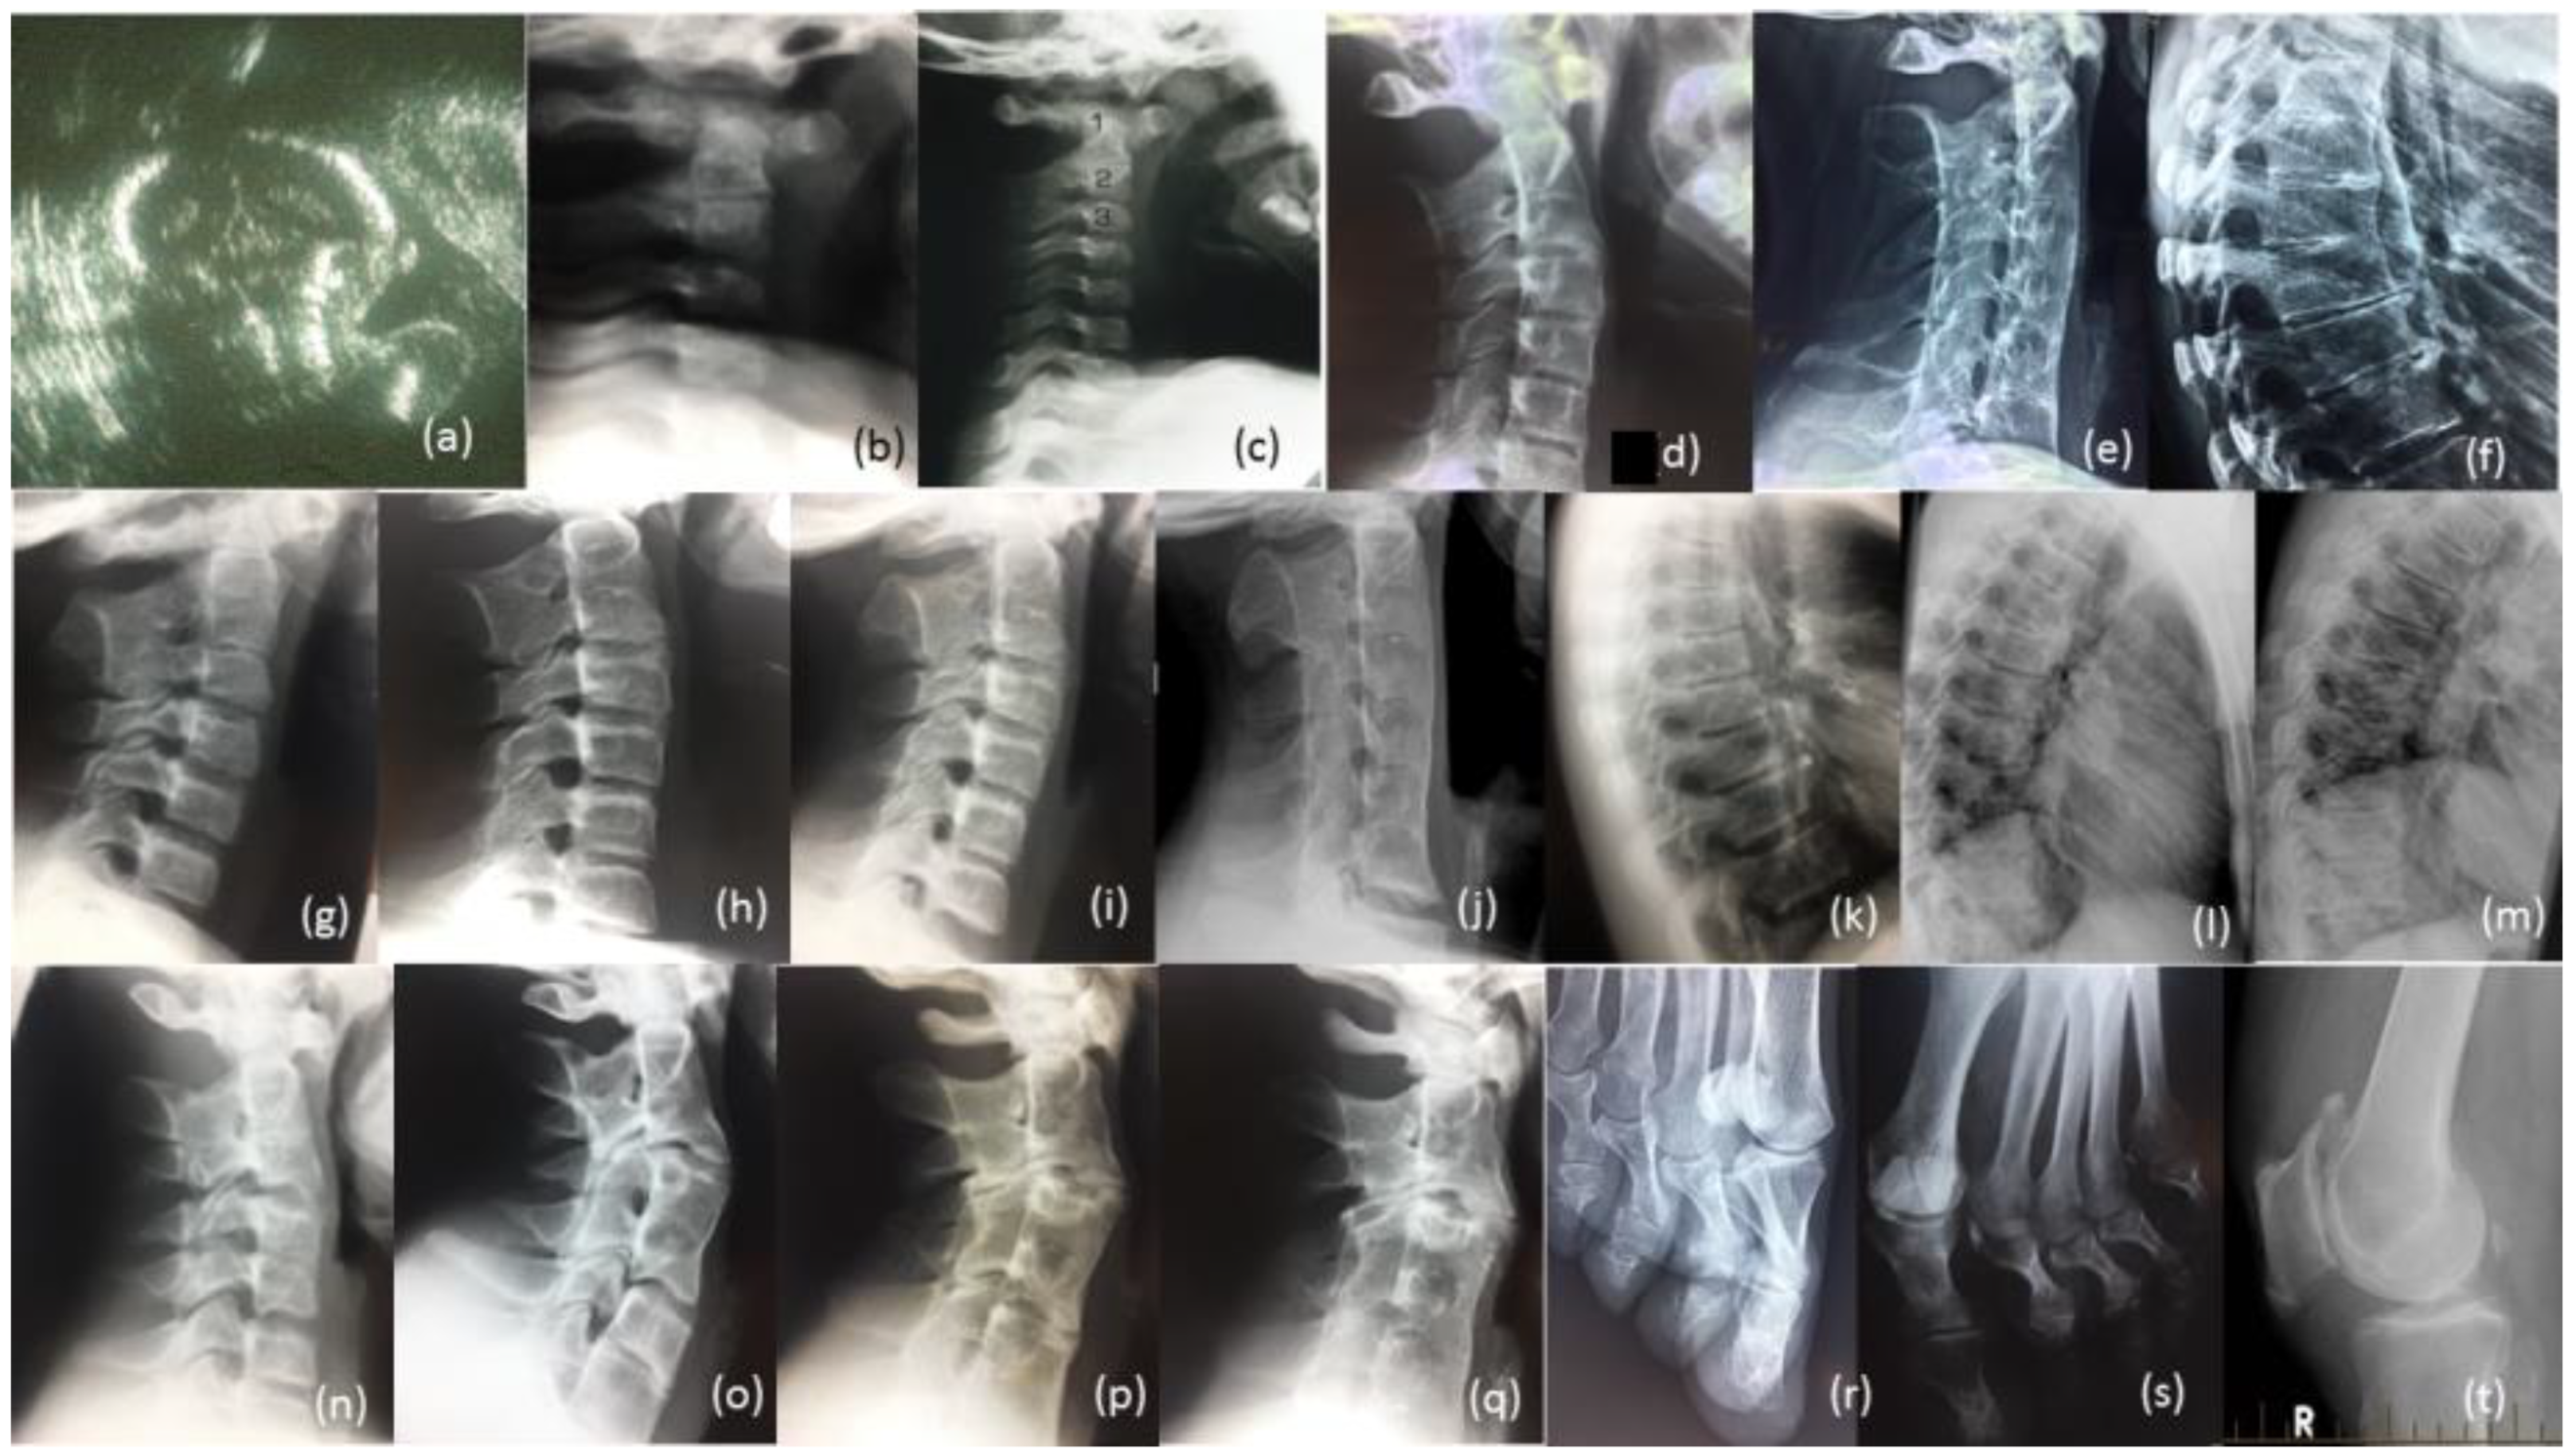

Figure 4.

Radiological review of family. Legend: (a) Prenatal ultrasound of cervical spine of proband 36 Weeks; (b) Radiographs of cervical spine of proband age 10 weeks, (c) 12 months (d) 13 years (e) 27 years; (f) Radiograph of thoracic spine of proband age 27 years; (g) Radiograph of cervical spine of brother IV-10 age 7 years, (h) age 14 years, (i) age 17 years, (j) age 26 years; (k) Radiograph of thoracic spine of IV-10 age 17 years, (l) age 26 years, (m) father III-6; (n) Radiograph of cervical spine of brother IV-9 age 12 years, (o) age 19 years, (p) cousin IV-5 age 17 years, (q) age 24 years; (r) Bilateral deviation of the proximal phalanges cousin IV, (s) aunty III-2, (t) Bilateral spurs on patella Aunty III-5 age 65 years.

The female proband presented with bilateral carpal and tarsal coalition. In the feet there was bilateral fusion between the navicular and cuboid. In the hands there was bilateral fusion between the triquetrum and lunate and between the hamate and capitate and partial fusion between the hamate and pisiform (Figure 2). Bilateral elongation of the pisiforms was symmetrically similar in the proband (Figure 3a) and all other affected family members tested, but varied greatly in degree between affected family members (Figure 3b). Pisiform elongation associated with restricted wrist rotation/supination and grasping and capacity to write. Prenatal ultrasound of the proband provided no evidence of vertebral fusion (Figure 4a). Spinal radiographs at age 10 weeks for the proband confirmed the absence of congenital vertebral fusion in the cervical spine (Figure 4b). At age 12 months the proband had developed fusion of the C2-3 apophyseal joints and anterior regions of the spinous processes (Figure 4c). At age 13 there was complete fusion of the C2-3 vertebral bodies, fusion of the anterior edges of C3-4 and C4-5 vertebral bodies, progressive ossification of the anterior edges between C5-6 vertebral bodies, partial fusion of the apophyseal joints and spinous processes at C6-7 (Figure 4d) and partial fusion of T3-7 vertebral bodies. At age 27 spinal fusion of the vertebrae had progressed to form block fusion across C2-7 (Figure 4e) and a continuous set of partial fusions of the anterior edges of the vertebral bodies between T3-T7 (Figure 4f). The bilaterally elongated pisiforms of the proband did not increase in length or size over time nor did the fusion of carpals or tarsals appear to progress. Pisiform elongation was associated with restricted flexion and supination movement of the wrist. The proband presented with stiffness in the Achilles tendon with associated toe walking. She was the only female (age 27) tested that was negative for hearing loss and she was dysphonic from birth and displayed severe speech impairment which was associated with malformation of laryngeal cartilages in her speech-impaired father. Short tongue and microstomia was evident in the proband and most other affected family members in association with overcrowding of the teeth that required teeth removal.

The youngest brother of the proband presented with bilateral fusion between the hamate and capitate and between the hamate and pisiform, but not between the lunate and triquetrum as observed in both the proband and her affected father. In addition, there was bilateral extension of the pisiform proximally that restricted supination of the wrists and apposition of the thumbs. There was bilateral fusion of the tarsals including cuneiform coalition and talocalcaneal coalition. Radiographs of the spine indicated progressive postnatal cranio-caudal acquisition of vertebral fusions beginning from C2-3. At age 7 this boy presented with fusion of the apophyseal joints and spinous processes of the 2nd and 3rd cervical (C2-3) vertebrae (Figure 4g) which by age 14 had progressed to complete fusion of the C2-3 vertebral bodies and thinning of the vertebral interspace at C3-4 (Figure 4h). At age 17 ossification of intervertebral disc spaces had progressed to where there was thinning of the C3-7 vertebral interspaces and fusion of the apophyseal joints at C2-6 on the right and C6-7 on the left (Figure 4i) which by age 26 had progressed to complete block fusion of C2-7 (Figure 4j). At age 26 he presented with vertebral fusion in the upper thoracic spine where there had only been thinning of these interspaces 9 years earlier (Figure 4k). At age 26 there was partial anterior fusion of the vertebral bodies at T4-T6 (Figure 4l) comparable to the thoracic fusion profile in the spine of his affected father III-6 (Figure 4m). Aged 7 years, he presented with very mild dysphonia, habitual toe walking, severely restricted flexion and supination movement in the hands, microtia, low set ears, short tongue, microstomia and overcrowding of the teeth that required teeth removal. Mobility of other joints appeared normal and there was no conductive hearing loss evident in this man or any other affected male member of the family.

3.1.3. Brother (IV-9)

The proband’s oldest brother (IV-9) presented with postnatal fusion in the cervical spine which progressed in a cranio-caudal direction from C2-3. A solitary C2-3 fusion identified at age 12 (Figure 4n) had progressed 7 years later to include a C4-5 fusion and thinning of the C6-7 interspace (Figure 4o). There was no evidence of conductive hearing loss in this brother or any other affected male members of the family. He suffered severe dysphonia from birth associated with severe speech impairment, microstomia and overcrowding of the teeth.

3.1.4. Male Cousin (IV-5)

The proband’s male cousin (IV-5) presented with progressive postnatal fusion of the cervical spine. Fusion of the C2-3, C4-5 and C6-7 cervical vertebrae at age 17 (Figure 4p) had progressed to C2-7 block fusion at age 24 (Figure 4q). At age 50 he experienced severe stiffness of the neck, shoulders and back. There was no evidence of conductive hearing loss. Severe speech impairment was evident from an early age. Short tongue and microstomia was associated with overcrowding of the teeth that required removal of eight teeth from him and all three of his affected sisters (IV-6, -7 and -8).

All four of the affected family members reviewed here in detail (Table 1) presented with progressive postnatal acquisition of vertebral fusions (Figure 4). Ultrasound before birth for two affected family members (IV-12 and V-3) confirmed the absence of congenital vertebral fusion which later developed postnatally through progressive ossification. Vertebral fusion, carpal and tarsal coalition, bilateral pisiform elongation and vocal impairment were all variable in extent between affected family members. Bilateral deviation of the proximal phalanges of toes 2–5 was evident in two affected female members of the family (IV-8, see Figure 4r) and (III-2, see Figure 4s). The former female’s mother (III-5) developed painful age-related bilateral spurs on the patella at age 65 (Figure 4t) and age-related conductive hearing impairment age 40. Other skeletal anomalies included Perthes of the hip in one teenage male in association with a minimal fusion bridge between the C2-3 vertebrae and no obvious speech impairment (V-3). There was no evidence of restriction of the elbows or the shoulders in affected family members. Most affected family members presented with varying degrees of speech impairment from a young age in association with malformation of laryngeal cartilages including flattening of the anterior commissure and shortening of the vocal cords [15]. Surgical intervention in one affected family member reported that the vocal cords were shorter, failed to meet in the midline, were of a different complexion/composition and did not vibrate normally and that other vocal ligaments were ossified [15]. Short tongue and microstomia with overcrowding of the teeth were common. In more severely speech-affected members of the family there were deficits in verbal fluency and significant difficulty in generating words beginning with a certain letter [15]. Stature and intelligence appeared within the normal limits for all affected family members. Speech and hearing impairment affected learning; pisiform expansion restricted wrist rotation supination and grasping and capacity to write; narrowing of the oesophageal and laryngeal canals restricted swallowing and anaesthetic intubation; Achilles tendon stiffness was associated with toe walking; and arthritis progressed with age in many of the affected family members.